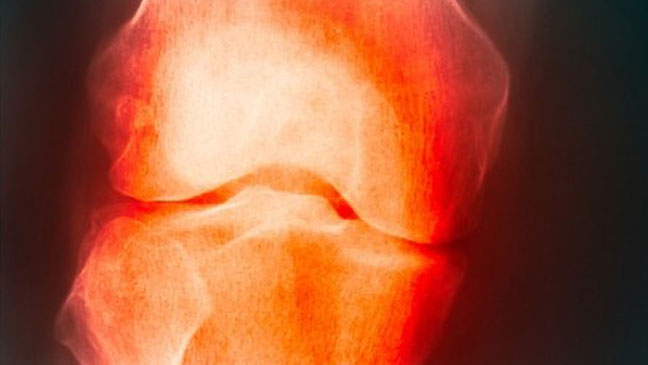

Osteoarthritis is one of the most common diseases people encounter as we age. Osteoarthritis is “wear and tear” arthritis. It occurs as microscopic damage occurs to the cartilage on the ends of the bones in our joints. The cartilage has a very limited ability to heal and as the damage to the cartilage occurs over time the cartilage becomes more and more rough losing its smoothness.

As the surface becomes more rough it tends to cause additional damage and accelerates the osteoarthritis. As the cartilage wears away the bone underneath sees increased stress and can become very hard or calcified. The bone recognizes this stress and tries to get bigger to spread the stress over a greater area and can form bone spurs or osteophytes near the joint.